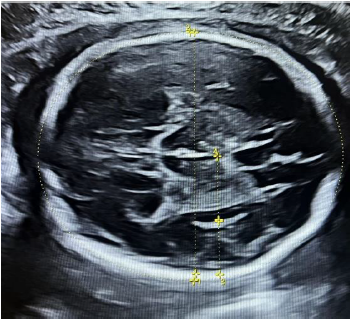

Measurement protocol: A standard transthalamic plane of the fetal head was used as the initial imaging plane for measuring BPD and HC. In this plane, the depths of the insula and Sylvian fissure were recorded (Figure 1). Subsequently, the probe was cranially adjusted to acquire a transventricular plane, where the depths of the POF, lateral ventricle, and the CSP width were measured (Figure 2).

Figure 2. Transventricular plane showing measurement of (1) ventricular diameter, (2) POF, and (3) CSPW